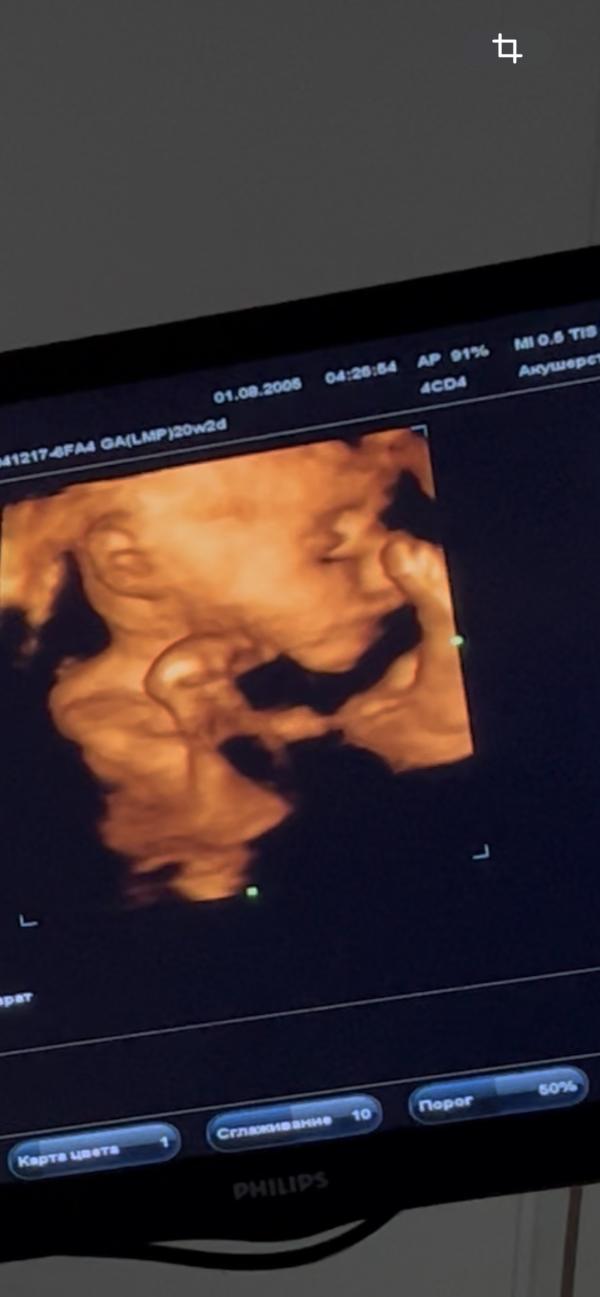

3D УЗИ при беременности: перекрытие губки у плода

Были сегодня на 3д узи

Все хорошо, малыш активно показывает ручки и уши, ухо у нас и правда отменное

Но меня смущает как нижнюю губку перекрывает верхняя

Надеюсь все будет хорошо

Искажение при узи) все нормально, я думаю

У них у всех верхняя губа огромная почему-то 😁